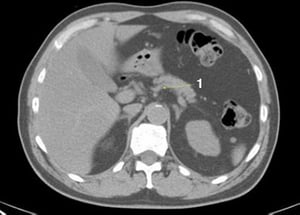

CT-Scan von Abdomen und Becken mit normaler Anatomie ohne Kontrastmittel (Folie 10)

Dieses Bild zeigt die Crura des Zwerchfells (Pfeile).

© Springer Science+Business Media